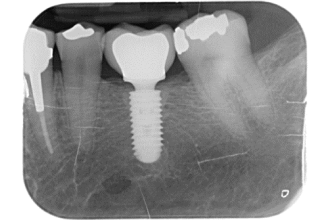

Les implants nous permettent de créer des racines artificielles sur lesquelles sont fixés des couronnes ou des appareils.

L’implant est une vis en titane que le chirurgien installe dans l’os des mâchoires. Il se soude peu à peu à l’os, un processus appelé ostéo-intégration. Le temps de guérison varie entre 4 et 6 mois selon la qualité de l’os et le type de restauration à faire.